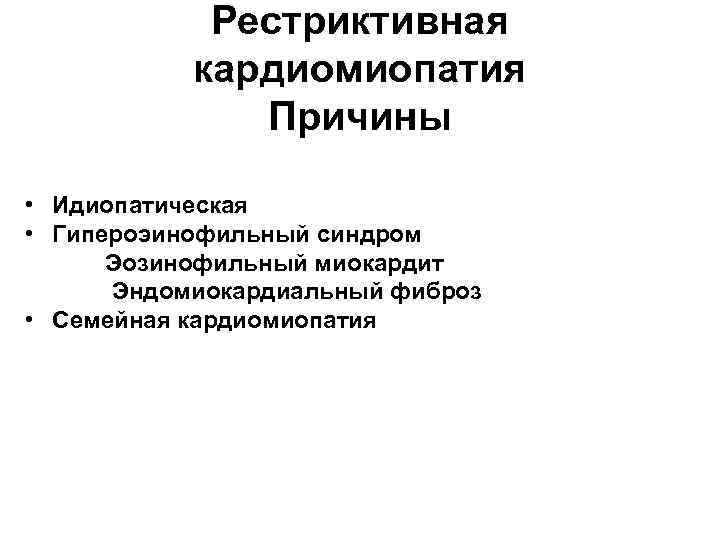

Рестриктивная кардиомиопатия Причины • Идиопатическая • Гипероэинофильный синдром Эозинофильный миокардит Эндомиокардиальный фиброз • Семейная кардиомиопатия

Рестриктивная кардиомиопатия Причины • Идиопатическая • Гипероэинофильный синдром Эозинофильный миокардит Эндомиокардиальный фиброз • Семейная кардиомиопатия